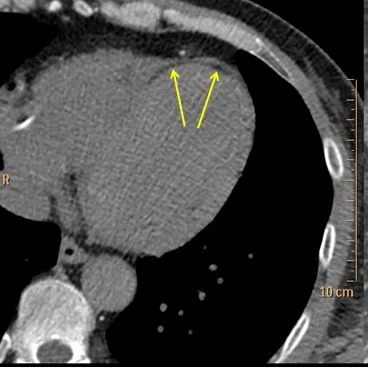

Conventional CT shows wall thinning and apparent hypoenhancement in the distal anterior wall and apex. On spectral images, using the virtual non-contrast image, we can tell there is deposition of fat in the subendocardium (negative HU values). Fat deposition is a common finding in old MI. There is also markedly decreased iodine uptake in the old MI, relative to the normal myocardium.

Virtual non-contrast: fat deposition in the subendocardium (yellow arrows).